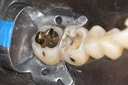

Gary Umeda #30 foil